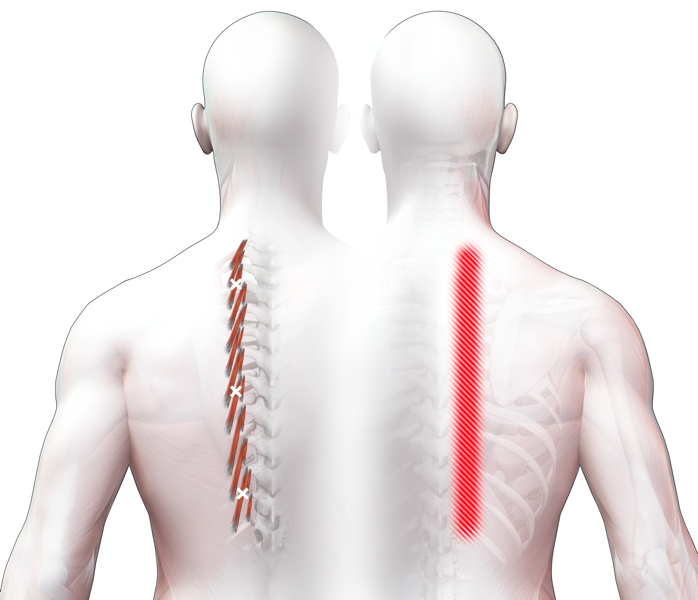

Spieren (Nederlands)

Spieren (nederlands)

Spieren (Latijn)

Spieren (latijn)